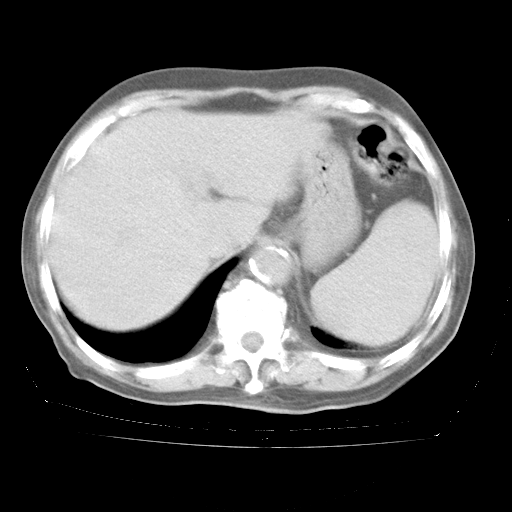

4月28日肺部CT——再次出现类似去年5月9日——透光度降低,“间质性”改变。

4月28日肺部CT

个人阅读4.14日肺部CT平扫:纵隔窗无异常,但肺窗示:双下肺内、后基底段有片絮状侵润影,部位以后基底段为著,以间质改变为主,呈急性肺泡炎征像,和首次住院影像学有相似之处。仅是个人读片,明日请相关专家再读片哈。其它建议同上。